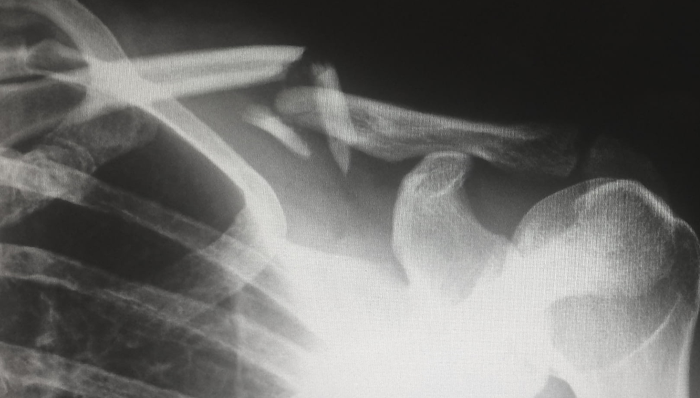

如下圖所示,在頸椎前路釘固定融合系統(tǒng)A組的報(bào)價(jià)中,入局者的報(bào)價(jià)極為接近。

在醫(yī)藥領(lǐng)域,進(jìn)口產(chǎn)品與國(guó)產(chǎn)產(chǎn)品價(jià)格相近是優(yōu)勢(shì),但在骨科耗材領(lǐng)域則是劣勢(shì)。因?yàn)樵诙▋r(jià)相近的情況下,成本更低的國(guó)產(chǎn)品牌能夠給予渠道更豐厚的利潤(rùn)。